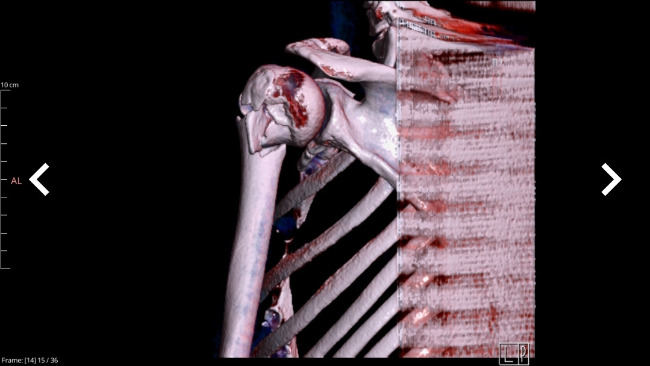

I underwent surgery at HCP Hospital in Poznań under the public healthcare system (NFZ). During the operation, my bone was stabilized with a metal rod and five screws, which gave my arm a chance to heal. I am currently waiting in a long queue for rehabilitation under the National Health Fund — my rehabilitation is scheduled for August 2026.

My arm also requires a second surgery, during which the screws will be removed. They turned out to be too long in relation to my slim arm structure and block the movement of my arm, making it impossible for me to lift it.